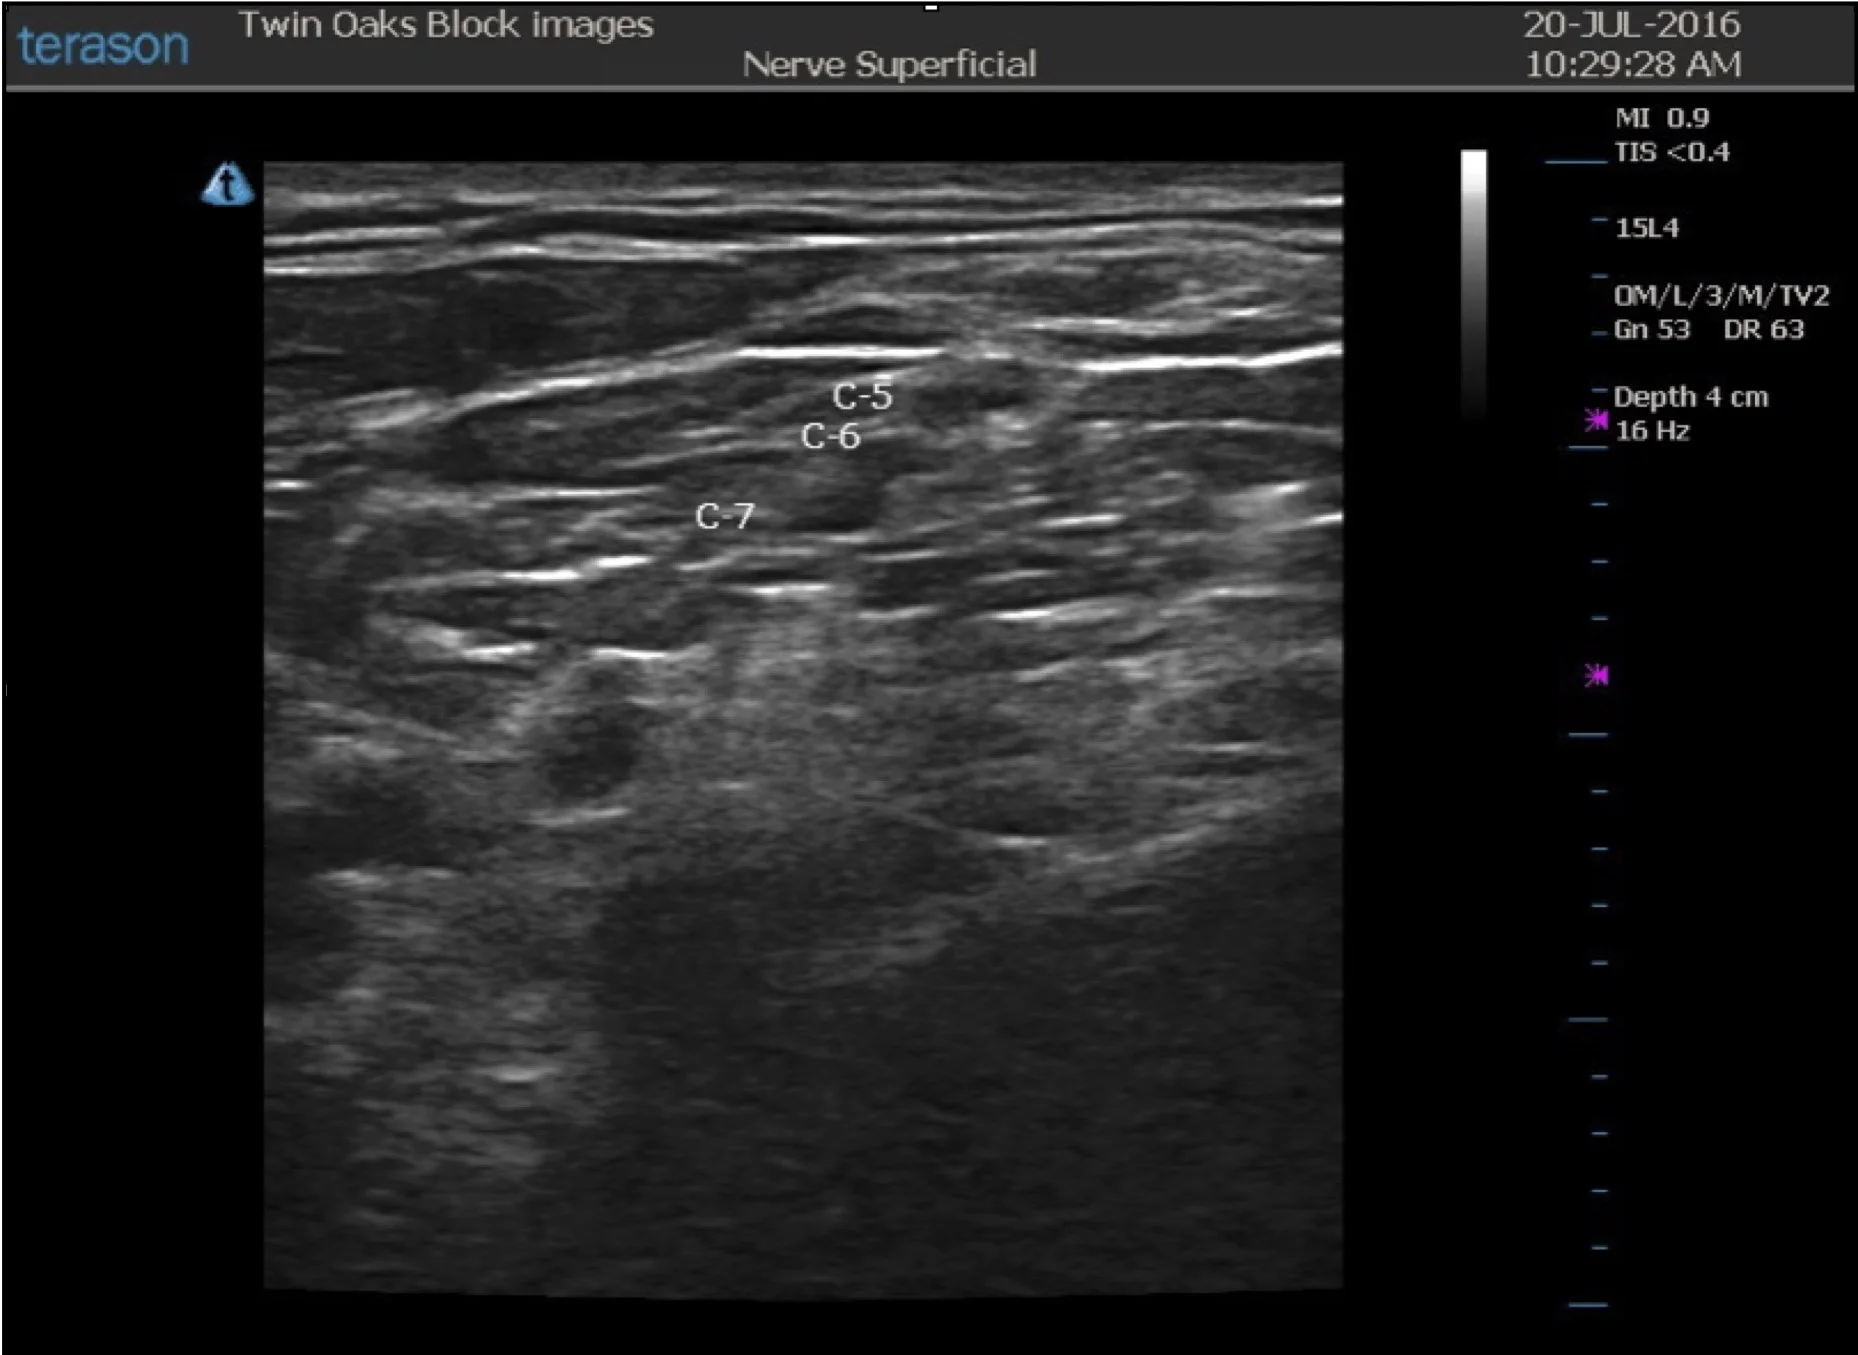

From www.twinoaksanesthesia.com

Interscalene Block — CRNA Conferences Twin Oaks Anesthesia What Is Interscalene Block the part of the brachial plexus that supplies your shoulder sits in a “groove” in your neck called the interscalene groove. The brachial plexus is commonly blocked at interscalene level for surgeries involving. the interscalene nerve block is a commonly performed regional anesthetic technique at the level of the upper trunks of the brachial plexus to. interscalene. What Is Interscalene Block.